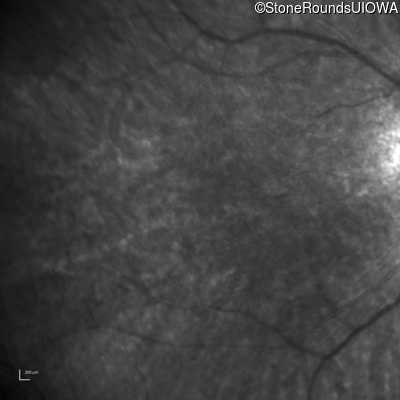

Age at visit: 10 years

Age at visit: 11 years

Age at visit: 12 years

Age at visit: 13 years

Age at visit: 14 years

Age at visit: 16 years